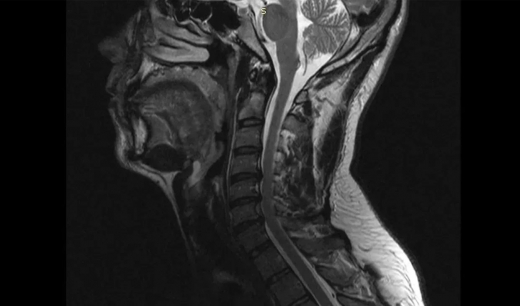

Нейрохирурги больницы скорой медицинской помощи №1 провели уникальную операцию, позволившую 38-летнему жителю Воронежа вновь свободно двигать руками. Об этом сообщило министерство здравоохранения Воронежской области. Пациент длительное время страдал из-за остеохондроза шейного отдела позвоночника. С августа 2025 года после физической нагрузки боль стала значительно сильнее и распространилась также на правую руку. К неприятным ощущениям добавились слабость и онемение. Консервативные методы лечения не дали результата, поэтому мужчину направили на операцию. В стационаре ему диагностировали диско-остеофитный стеноз позвоночного канала на уровне нескольких шейных позвонков. Это означает, что произошло сужение канала, а расположенные в нем структуры оказались сдавленными. Коллектив врачей под руководством заведующего нейрохирургическим отделением Павла Юрова провел операцию, особенность которой состоит в применении комбинированной техники.  Воронежцу устранили компрессию и выполнили стабилизацию позвоночника, одновременно усилив его различными титановыми конструкциями. Спустя три часа после вмешательства пациент уже мог подниматься на ноги. Болевые ощущения уменьшились, в мышцах восстановилась сила — онемение практически перестало беспокоить. Мужчина был выписан на пятые сутки после операции, после чего ему предстояло лечение в реабилитационном отделении. 26 марта "TV Губерния" сообщала, что воронежские врачи спасли полуторагодовалую девочку от удушья. У неё в носоглотке застрял магнит.